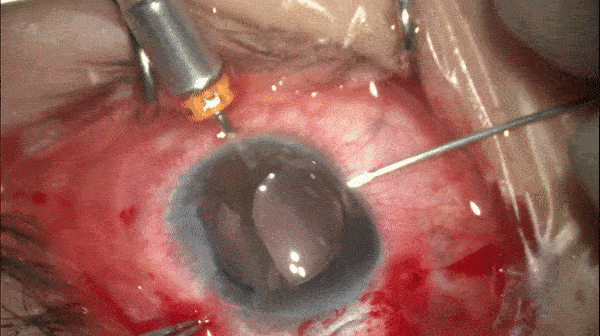

开睑器怎么用术说睛彩 | 金海鹰教授:使用8-0缝线的无巩膜瓣人工晶体固定手术_https://www.jmylbn.com_新闻资讯_第6张

注入IOL并将另一侧晶体襻留置于眼外。